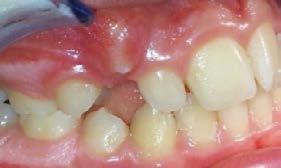

La incidencia de inclusión en los caninos superiores e inferiores tiene diferentes etiologías y similitudes. En ambos casos, el motivo principal se deriva de razones propias por su anatomía, tamaño en volumen coronal y largo de la raíz; sumado a esto, su ubicación lejana intraósea respecto al arco dental, desde la germinación y/o inicio de formación y desarrollo y, hasta alcanzar la erupción (Figura 4).

Respecto a los caninos inferiores permanentes, presentan con mayor frecuencia una posición con mayor tendencia a la inclusión, en el aspecto bucal del arco dental que los superiores, según se muestra en estadísticas con valores de 4% de prevalencia.45

El trayecto que el canino tiene que recorrer desde su germinación hasta su acomodo final en el arco dental, es largo y complicado, al sortear barreras, alteraciones y modificaciones no previstas, surgidas de factores fuera del proceso natural, (entiéndase esto, como una alteración al código preprogramado del proceso de crecimiento y desarrollo craneodentofacial, por factores externos al organismo), antes de lograr erupcionar y en ocasiones sin obtener oclusión con su antagonista (Figura 5).